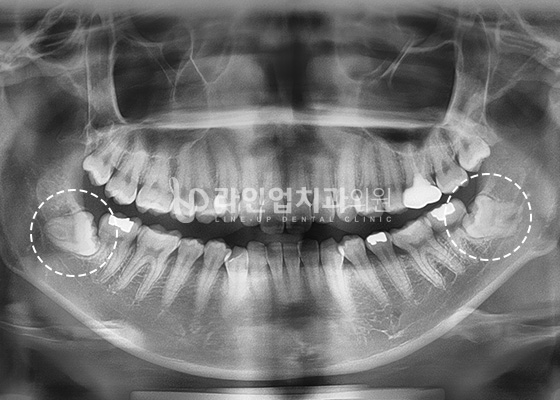

Агт арааны эмчилгээний өмнө ба дараах зураг

After